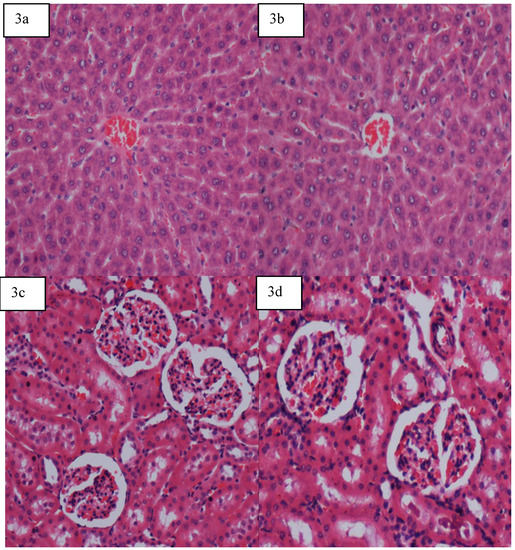

2.5.4. Gross Necropsy and Histology

There was no significant decrease or increase in levels of all parameters of males as well as females groups in all dosages, as shown in Figure 3(a) to 3(d).

Figure 3. Histology and pathology snapshots of (3a) liver tissue in a rat pre-treated with vehicle (distilled water) showed normal appearance, (3b)liver tissue in a rat pre-treated with 5 mg/kg adiponectin showed normal appearance(3c) kidney tissue in a rat pre-treated with vehicle (distilled water) showed normal appearance (3d) kidney tissue in a rat pre-treated with 5 mg/kg adiponectin showed normal structural appearance.